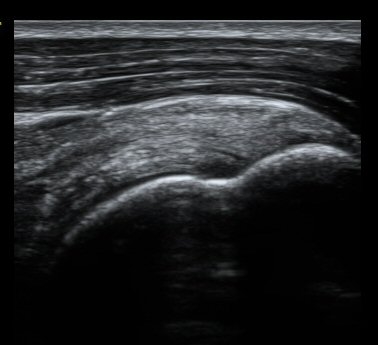

ȸÀü±Ù°³°£°Ý Ⱦ´ã³à°Ë»ç¿¡¼­ ƯÀÌ ¼Ò°ßÀ» º¸ÀÌÁö ¾ÊÀ½(±×¸² 1).

À̵ιڱٰí¶û¿¡¼­ À̵ιڱÙÀÌ Á¤»óÀûÀ¸·Î °üÂûµÇ°í ƯÀÌ ¼Ò°ßÀ» º¸ÀÌÁö ¾ÊÀ½(±×¸² 2).